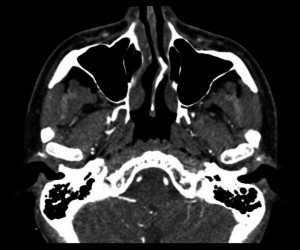

Scanner cérébral

Scanner des sinus

Scanner ORL